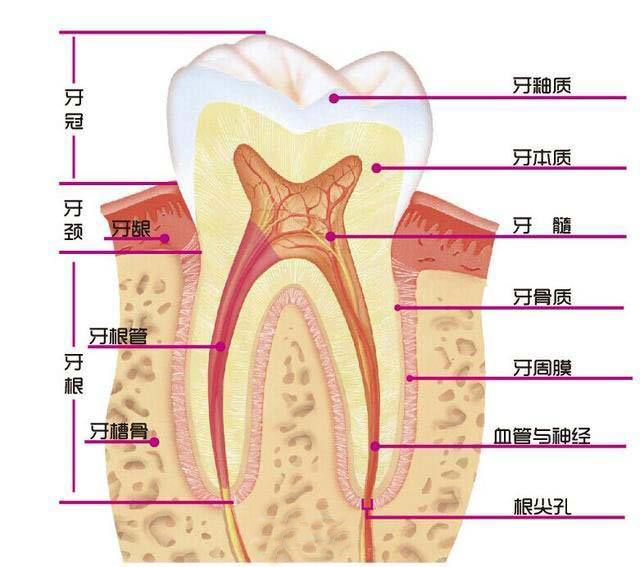

龋齿的分类:根据病变深度可分为浅龋、中龋、深龋。

①浅龋:病变限于牙釉质或牙骨质,患者一般无主观症状。

②中龋:病变已达牙本质浅层,明显龋洞。患者遇冷热酸甜较敏感,但去除刺激因素后症状立即消失。

③深龋:病变已达牙本质深层,一般表现为大而深的龋洞。对外界刺激反应较中龋为重,但刺激源去除后,仍可立即止痛,无自发性痛。

牙隐裂

- 牙隐裂,又称微裂,一般是指牙齿表面有特别微细的不易被发现的异常裂纹,由浅至深可以到达牙髓,最后导致牙齿的劈裂。患者常伴有牙本质过敏症状,长期的咬物疼痛,甚至可以呈撕裂样牙痛。多发生于上颌磨牙,其次是下颌磨牙和上颌前磨牙。